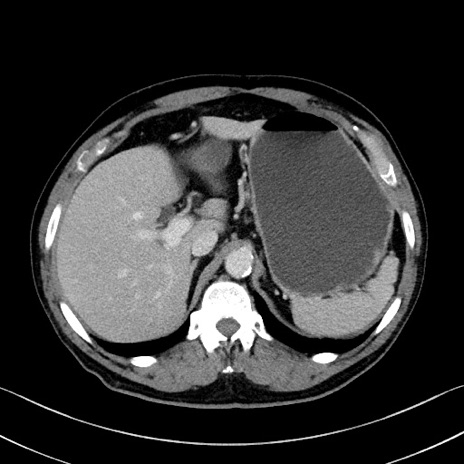

症例35(横断像)

【症例】70歳代 男性

【主訴】腹部膨満、嘔吐

【現病歴】昨日より腹部膨満感出現。本日増悪し、仙痛出現。嘔吐あり、受診。

【既往歴】糖尿病、胆摘後

【身体所見】BP 149/80mmHg、HR 74/min、BT 35.9℃、腹部:膨満、軟、圧痛なし。腸雑音減弱あり。上腹部正中切開瘢痕あり。

【データ】WBC 13500、CRP 1.72